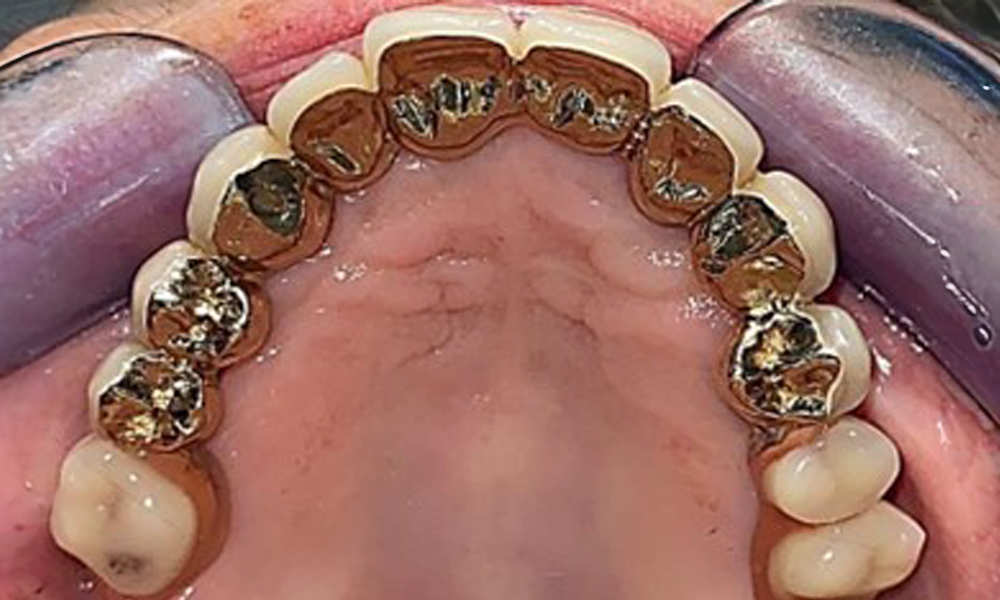

The dental findings are as follows: Combined removable implant and tooth-supported telescopic prostheses on implants 15, 13, 21, 23, 24, 25 and tooth 11 (Fig. 1, Fig. 2, Fig. 3). The patient was fitted with a fixed mandibular denture. Adequate bridges were present over 37 to 34 and 45 to 47 (Fig. 4), the crown margins were intact and there were no active caries. A composite filling with a marginal gap was present on tooth 43. There was mandibular gingival recession, exposing 1 to 3 mm of root surface. This also applies to 11.

Occlusal view: Maxilla with tooth and implant-supported telescopic prostheses.

Fig. 2: Occlusal view: Maxilla with tooth and implant-supported telescopic prostheses

Occlusal view: Maxilla with removable, palateless denture.

Fig. 3: Occlusal view: Maxilla with removable, palateless denture.